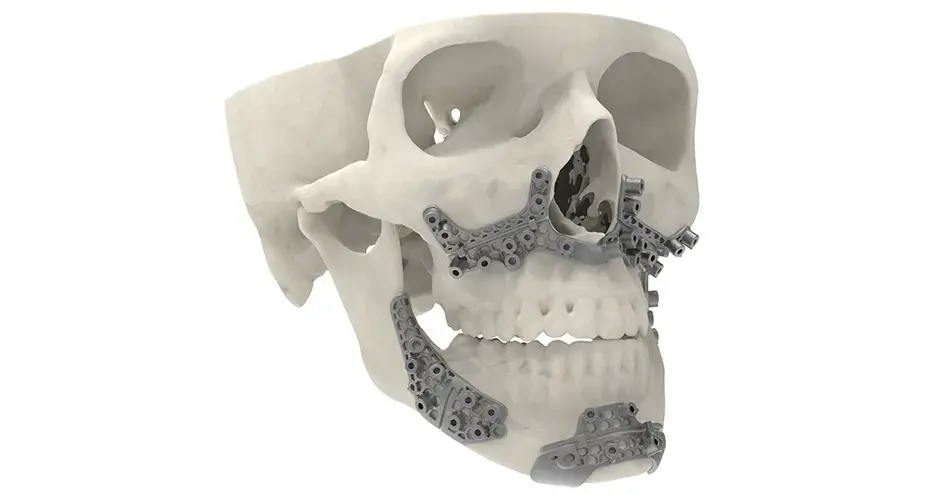

3D Systems' VSP® surgical planning solutions for craniomaxillofacial (CMF) applications received FDA clearance as a service-based approach to personalized surgery over 10 years ago.

3D Systems and Stryker Corporation have partnered to provide surgeons with best-in-class products and services for craniomaxillofacial surgeries. As a leader in personalized healthcare solutions, 3D Systems has planned and delivered devices for more than 140,000 patient-specific cases. The Stryker Craniomaxillofacial business specializes in providing patient-specific options and innovative solutions that help drive efficiencies in surgical suites. The combination of Stryker’s specialized team and advanced implants with 3D Systems' cutting-edge 3D printing technologies and expert consulting services positions both companies to provide a superior level of service to healthcare professionals who use these revolutionary solutions.